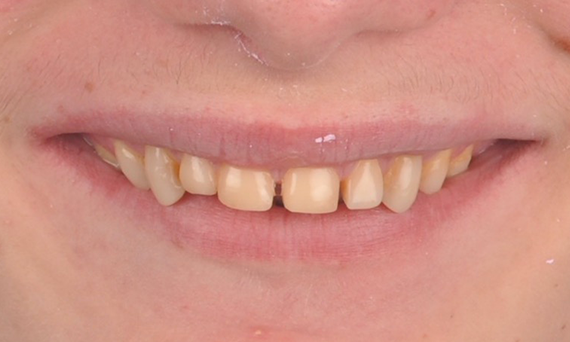

Réhabilitation esthétique d’une amélogenèse imparfaite

CEREC Tessera

Une restauration esthétique dans la région antérieure a pu être réalisée avec des restaurations CEREC Tessera en laboratoire, facettes en Celtra Ceram .

Avant : l’objectif du traitement était de réhabiliter le maxillaire antérieur et la mandibule pour une amélioration esthétique. Le diagnostic clinique a révélé une ameloenesis imperfecta.

Après : restauration fabriquée en laboratoire à partir de la céramique avancée au disilicate de lithium CEREC Tessera et, pour un résultat esthétique élevé, facettes en Celtra Ceram.